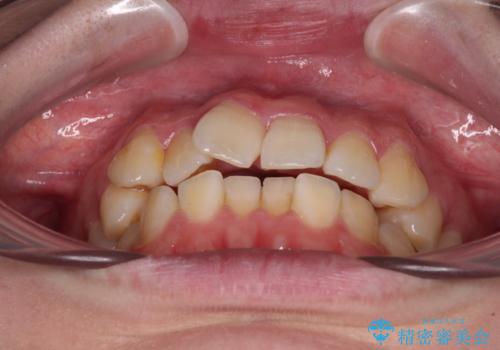

【モニター】八重歯を片側の抜歯矯正で治す メタルブラケット装置

- 八重歯とずれた正中を気にして来院された患者様です。

非抜歯矯正ではデコボコを解消することでより口元が突出する可能性があるため、上顎右右側の小臼歯1本の抜歯を行い、ワイヤー装置による矯正治療を行うこととしました。

正中位置を合わせるために、上顎臼歯部にアンカースクリューを埋入することとしました。